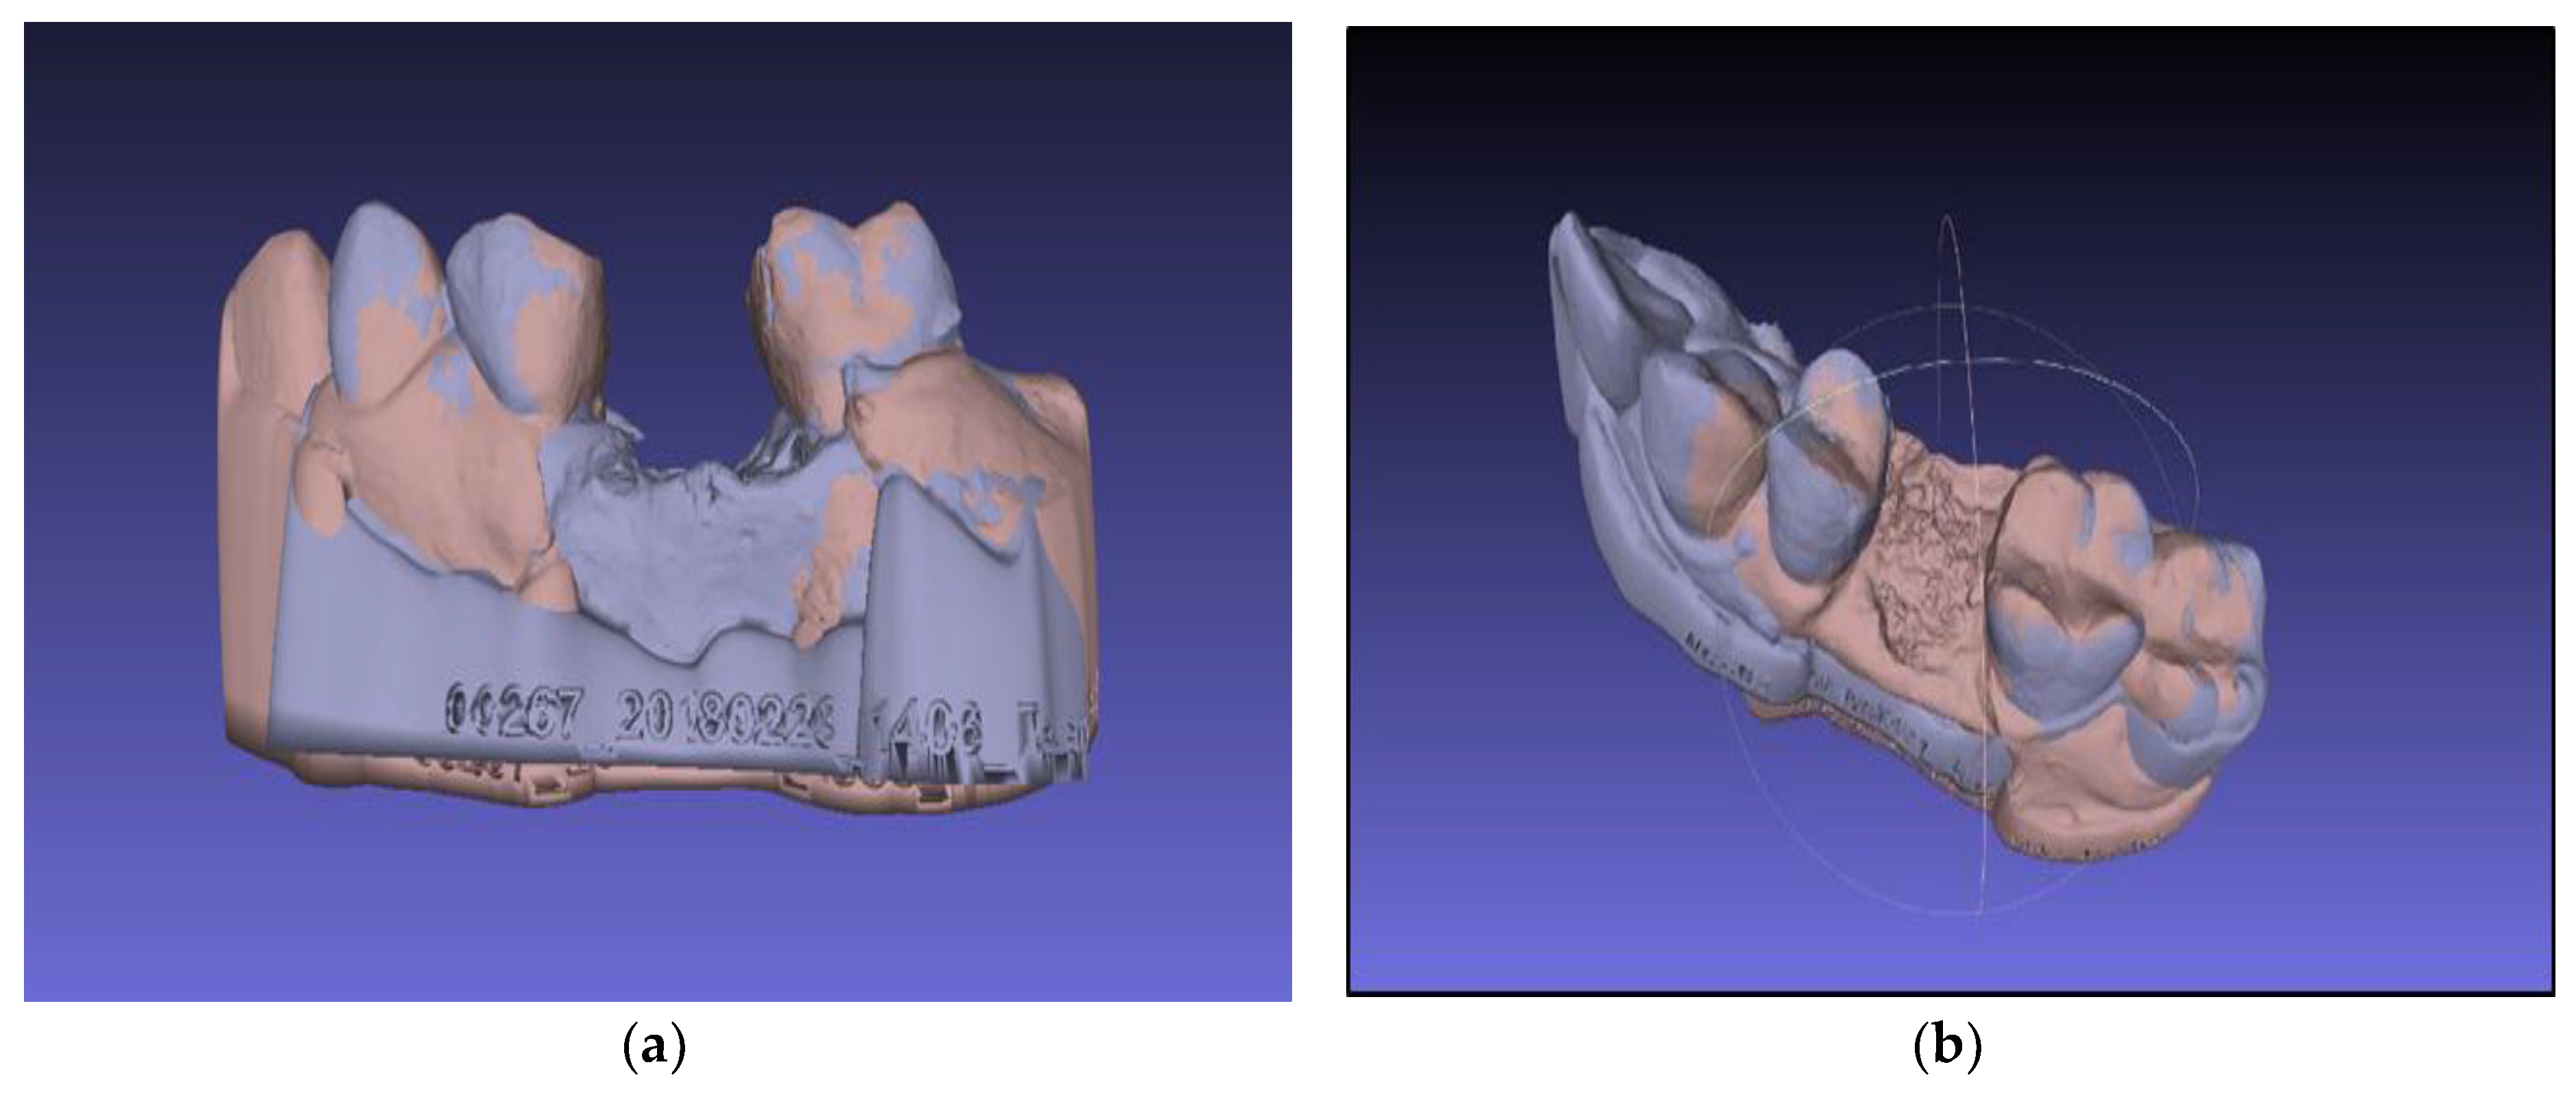

- Selection of the base model—choose a model that is tightly oriented at the base of the work area defined by the axes “x” and “y”

- Fix the selected model using the “Glue mesh here” command

- Equation of points with the point-based gluing function

- Selection of the “processing” function, by which the models are finely tuned by the “ICP—iterative closest point” method

3.2. Virtual Models Analysis